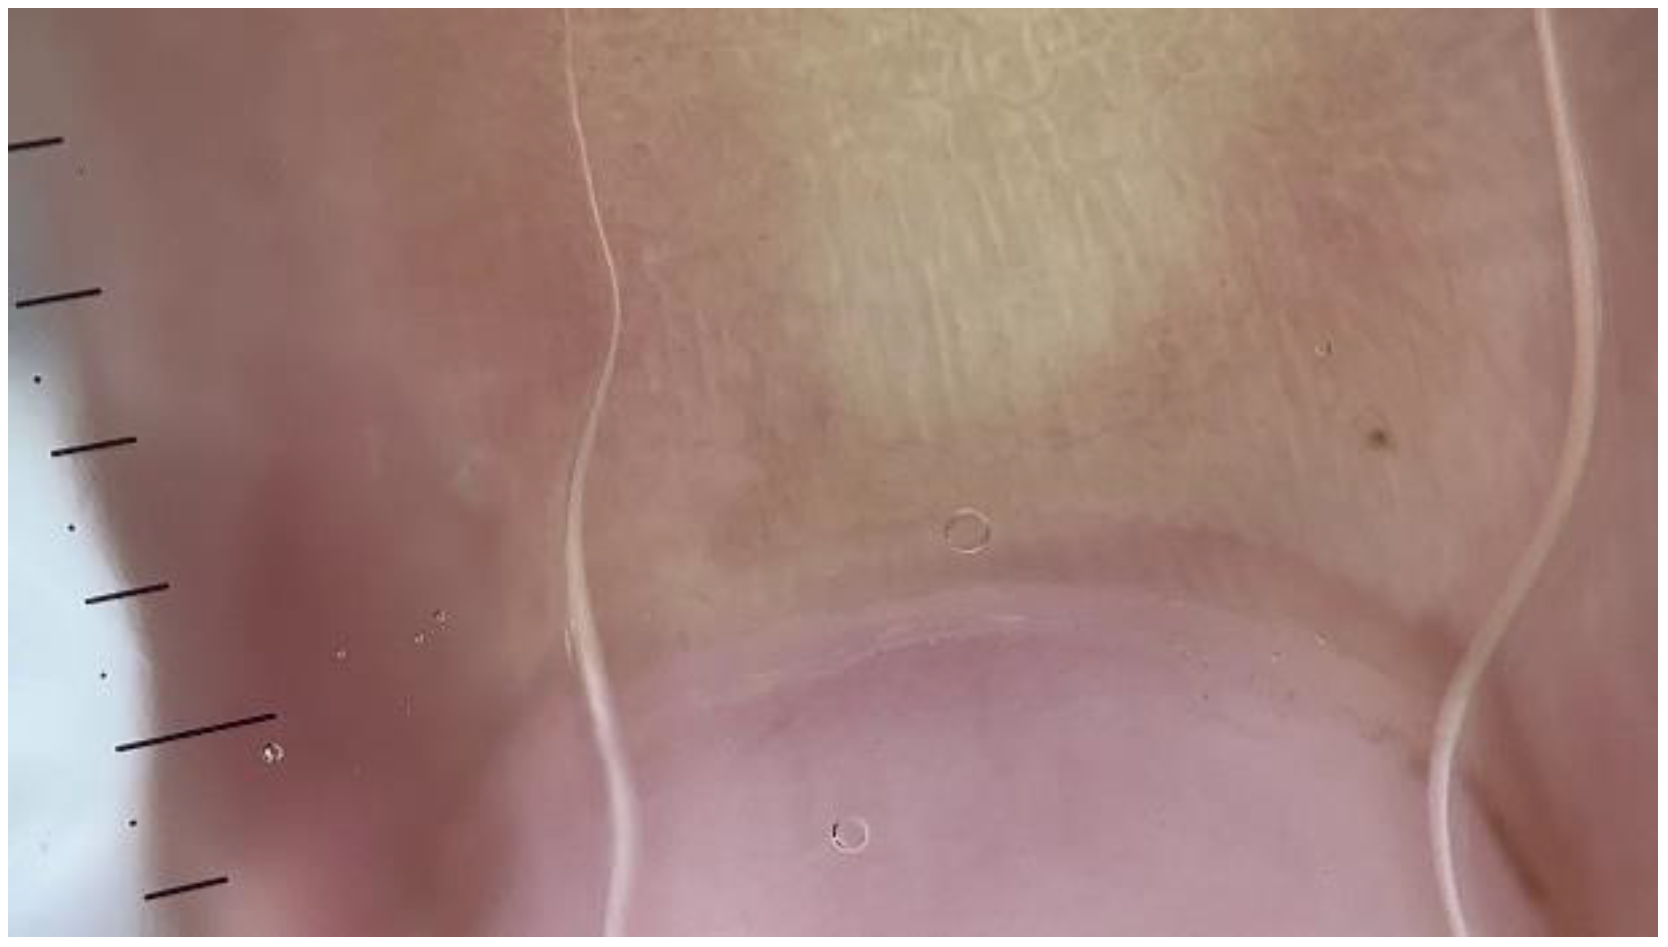

2.2. Findings